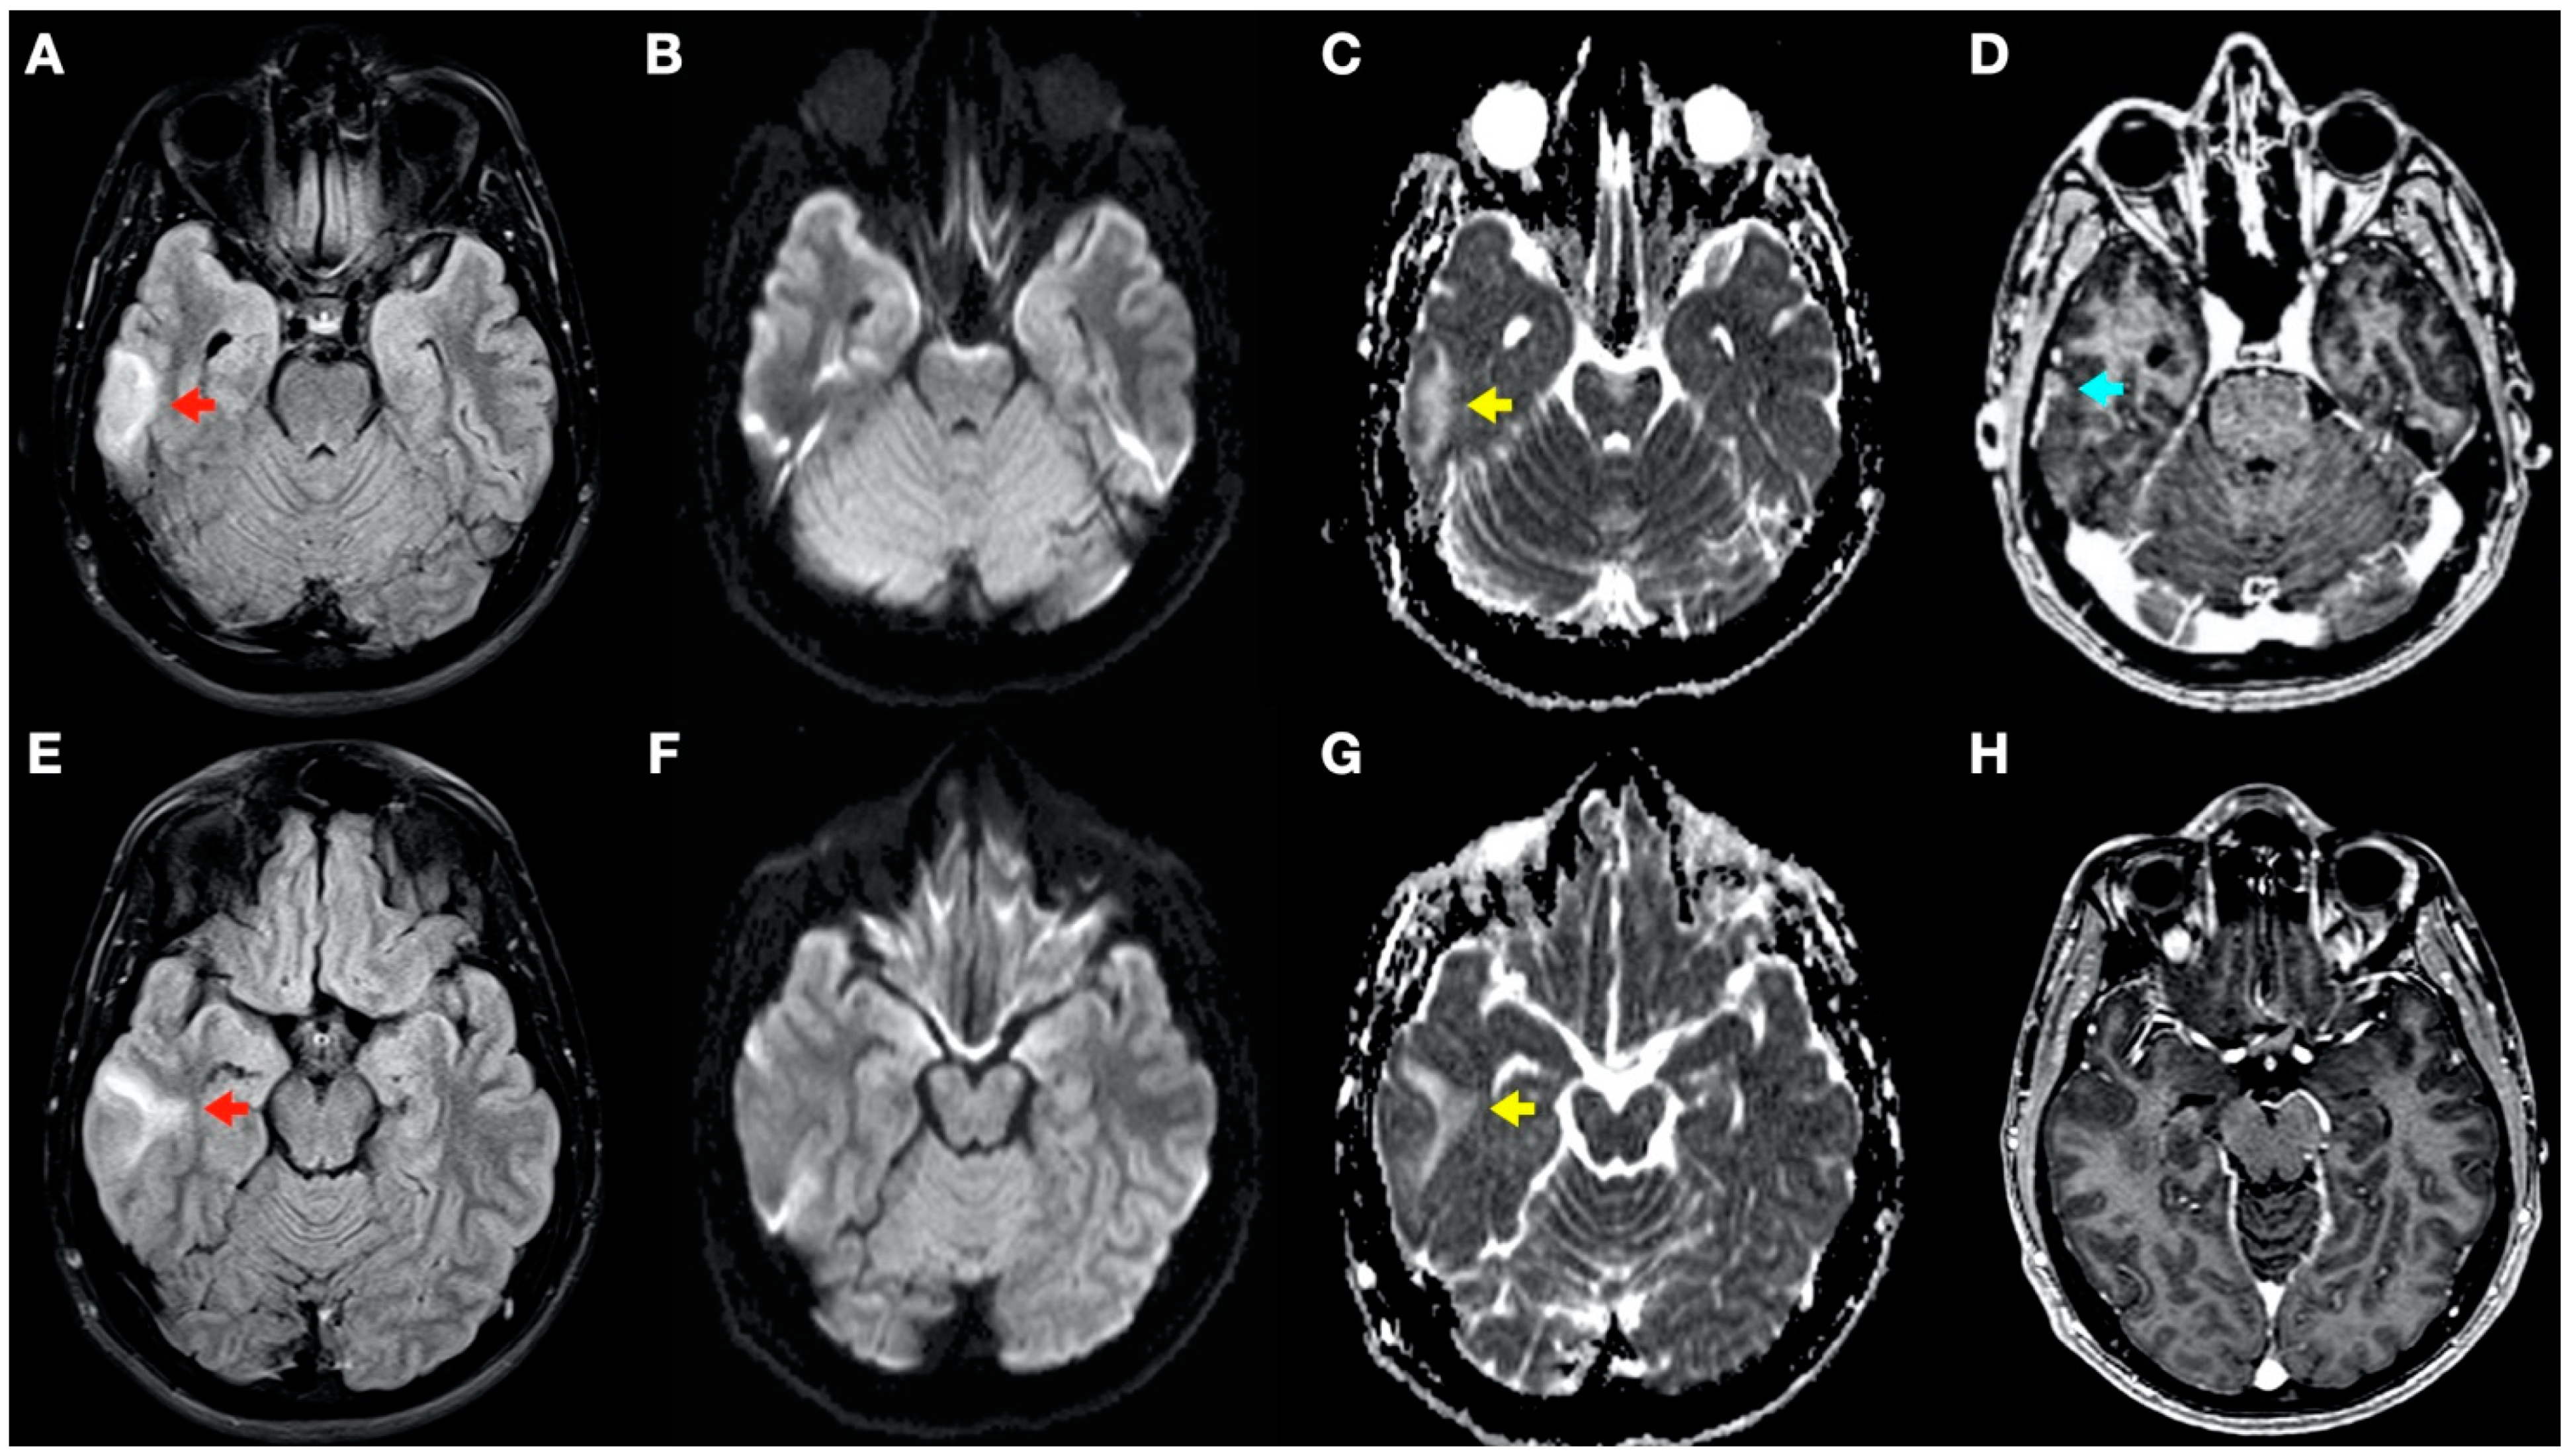

During admission, the following complementary examinations were performed: brain magnetic resonance imaging (MRI; Figure 3, Figure 4 and Figure 5) showed right temporal and left frontal cortico-subcortical lesions, probably secondary to neurological involvement of DCS; neurosonological study of supra-aortic and intracranial arteries showed no atheromatosis or significant hemodynamic alterations; blood tests, including biochemistry, hemogram, coagulation study, serology and autoimmunity, were normal; transthoracic echocardiography was normal (including negative agitated saline contrast study for right-to-left shunt); and total body CT scan showed no evidence of neoplastic process.

Figure 4.

Brain magnetic resonance imaging (MRI): Images (A–C,E–G) from MRI 4 days after clinical onset; images (D,H) from MRI 5 days after clinical onset. Axial fluid-attenuated inversion recovery (FLAIR) images (A,E) show a right temporal cortico-subcortical hyperintense lesion with slight mass effect (red arrows). Axial diffusion-weighted imaging (DWI) sequences (B,F) did not show a high-signal intensity of lesions, whereas axial apparent diffusion coefficient maps (C,G), show a hyperintense lesion in this location (yellow arrows). (D,H) Axial gadolinium-enhanced 3D T1-weighted imaging (Gd T1WI) shows the presence of a slight enhancement of irregular morphology (blue arrow).

In this complex scenario, we report an uncommon case of DCS in a spearfishing breath-hold diver. The diver had a high-risk dive profile, with repetitive breath-hold dives to a maximum depth of about 30 m for several hours and short surface intervals. He had a good response to hyperbaric chamber treatment (US Navy Table 6) and was clinically asymptomatic. Neuroimaging findings showed hyperintensity in long-TR sequences (FLAIR, T2WI), as well as in ADC mapping, and no hyperintensity in DWI sequences, compatible with the presence of vasogenic edema in the left frontal and right temporal lobes (Figure 3 and Figure 4). Regarding MRI perfusion, in the contrast enhancement area, there was an increase in cerebral blood volume (CBV) in relation to the contralateral side and normal subcortical white matter. In the average curves, the area under the curve was higher in the enhancement zone than in the other two zones, which would indicate an increase in perfusion (Figure 5). Initially, given the atypical nature of the lesions, with irregular enhancement in T1WI with intravenous contrast (although their radiological characteristics were not suggestive of neoplastic etiology) [22,23], an extension study with body CT was completed, showing no presence of neoplasia. Likewise, prior to the neuroimaging study, a vascular study (neurosonological, echocardiographic) was performed, as was an extensive blood test study, with no pathological findings. The radiological evolution of the lesions tended towards resolution, with minimal chronic lesions persisting, compatible with small areas of cerebral malacia (Figure 6).